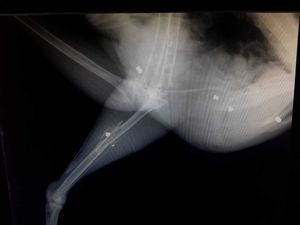

The peacock was rushed to the Stapeley Grange Wildlife Hospital in Cheshire for treatment where x-rays revealed an airgun pellet had completely shattered the bird's left leg. Vets also found a further five bullets that had gone through the bird's body in several places, causing severe damage to muscles and tendons.